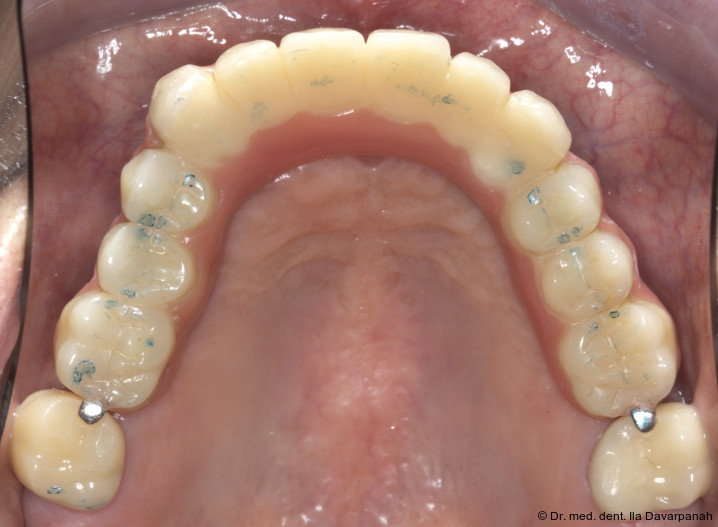

Auf Basis des digitalen Mock-ups wurden die Zirkonoxid-Primärkappen, galvanisch hergestellten Sekundärkappen sowie das NEM-Tertiärgerüst laborseitig gefertigt (Abb. 13+14). Die intraorale Verklebung der Sekundärkappen mit dem Tertiärgerüst erfolgte spannungsfrei im Mund (Abb. 15–17).

Eingliederung der Reise- und Definitivprothese

Nach Verkleben der sekundären Galvanokappen mit dem Tertiärgerüst verbleiben die Primärzirkonkappen im Mund. Um dem Patienten auf Basis dieser Pfeiler eine Interimsversorgung geben zu können, wird eine sogenannte Reiseprothese mit der Ästhetik und Funktion der finalen Versorgung hergestellt, welche auch als Referenz hierfür dient (Abb. 18+19).

Die definitive Prothese konnte im dritten Behandlungstermin problemlos eingegliedert werden. Es waren lediglich minimale okklusale Anpassungen erforderlich (Abb. 20–24).